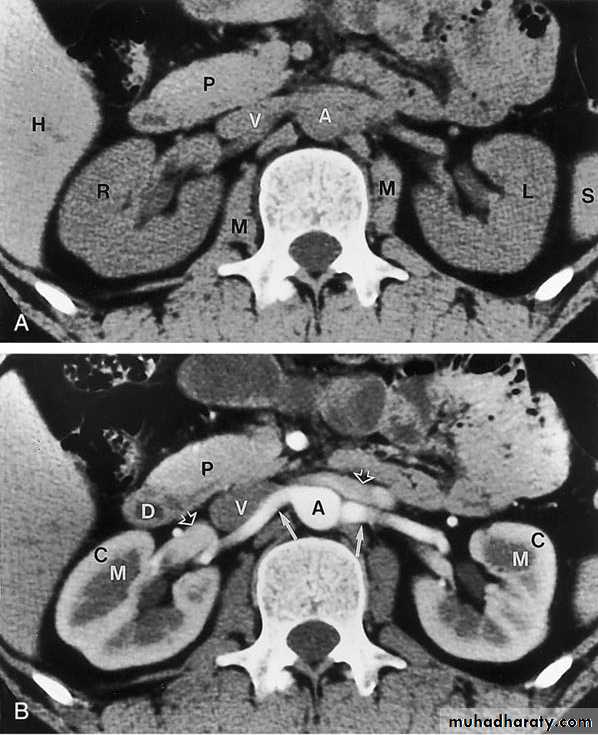

COMPUTED TOMOGRAPHY ( CT scan)

Non Contrasted (Native, non enhanced)Contrasted: Oral Contrast Agents

Intravenous Contrast Agents

CT scan accurately characterize the nature of tissue in the lesion.

CT is useful in the preoperative evaluation and staging of tumors.CT has replaced IV urography as the primary modality for the assessment of suspected renal injuries and their complications

For the evaluation of patients with acute flank pain, unenhanced spiral CT is more sensitive in detecting calculi than EXU. (except indinaver no radiolucent stones).

Drawbacks: Expensive, more radiation, not always available, need experience, contrast contraindications, pregnancy